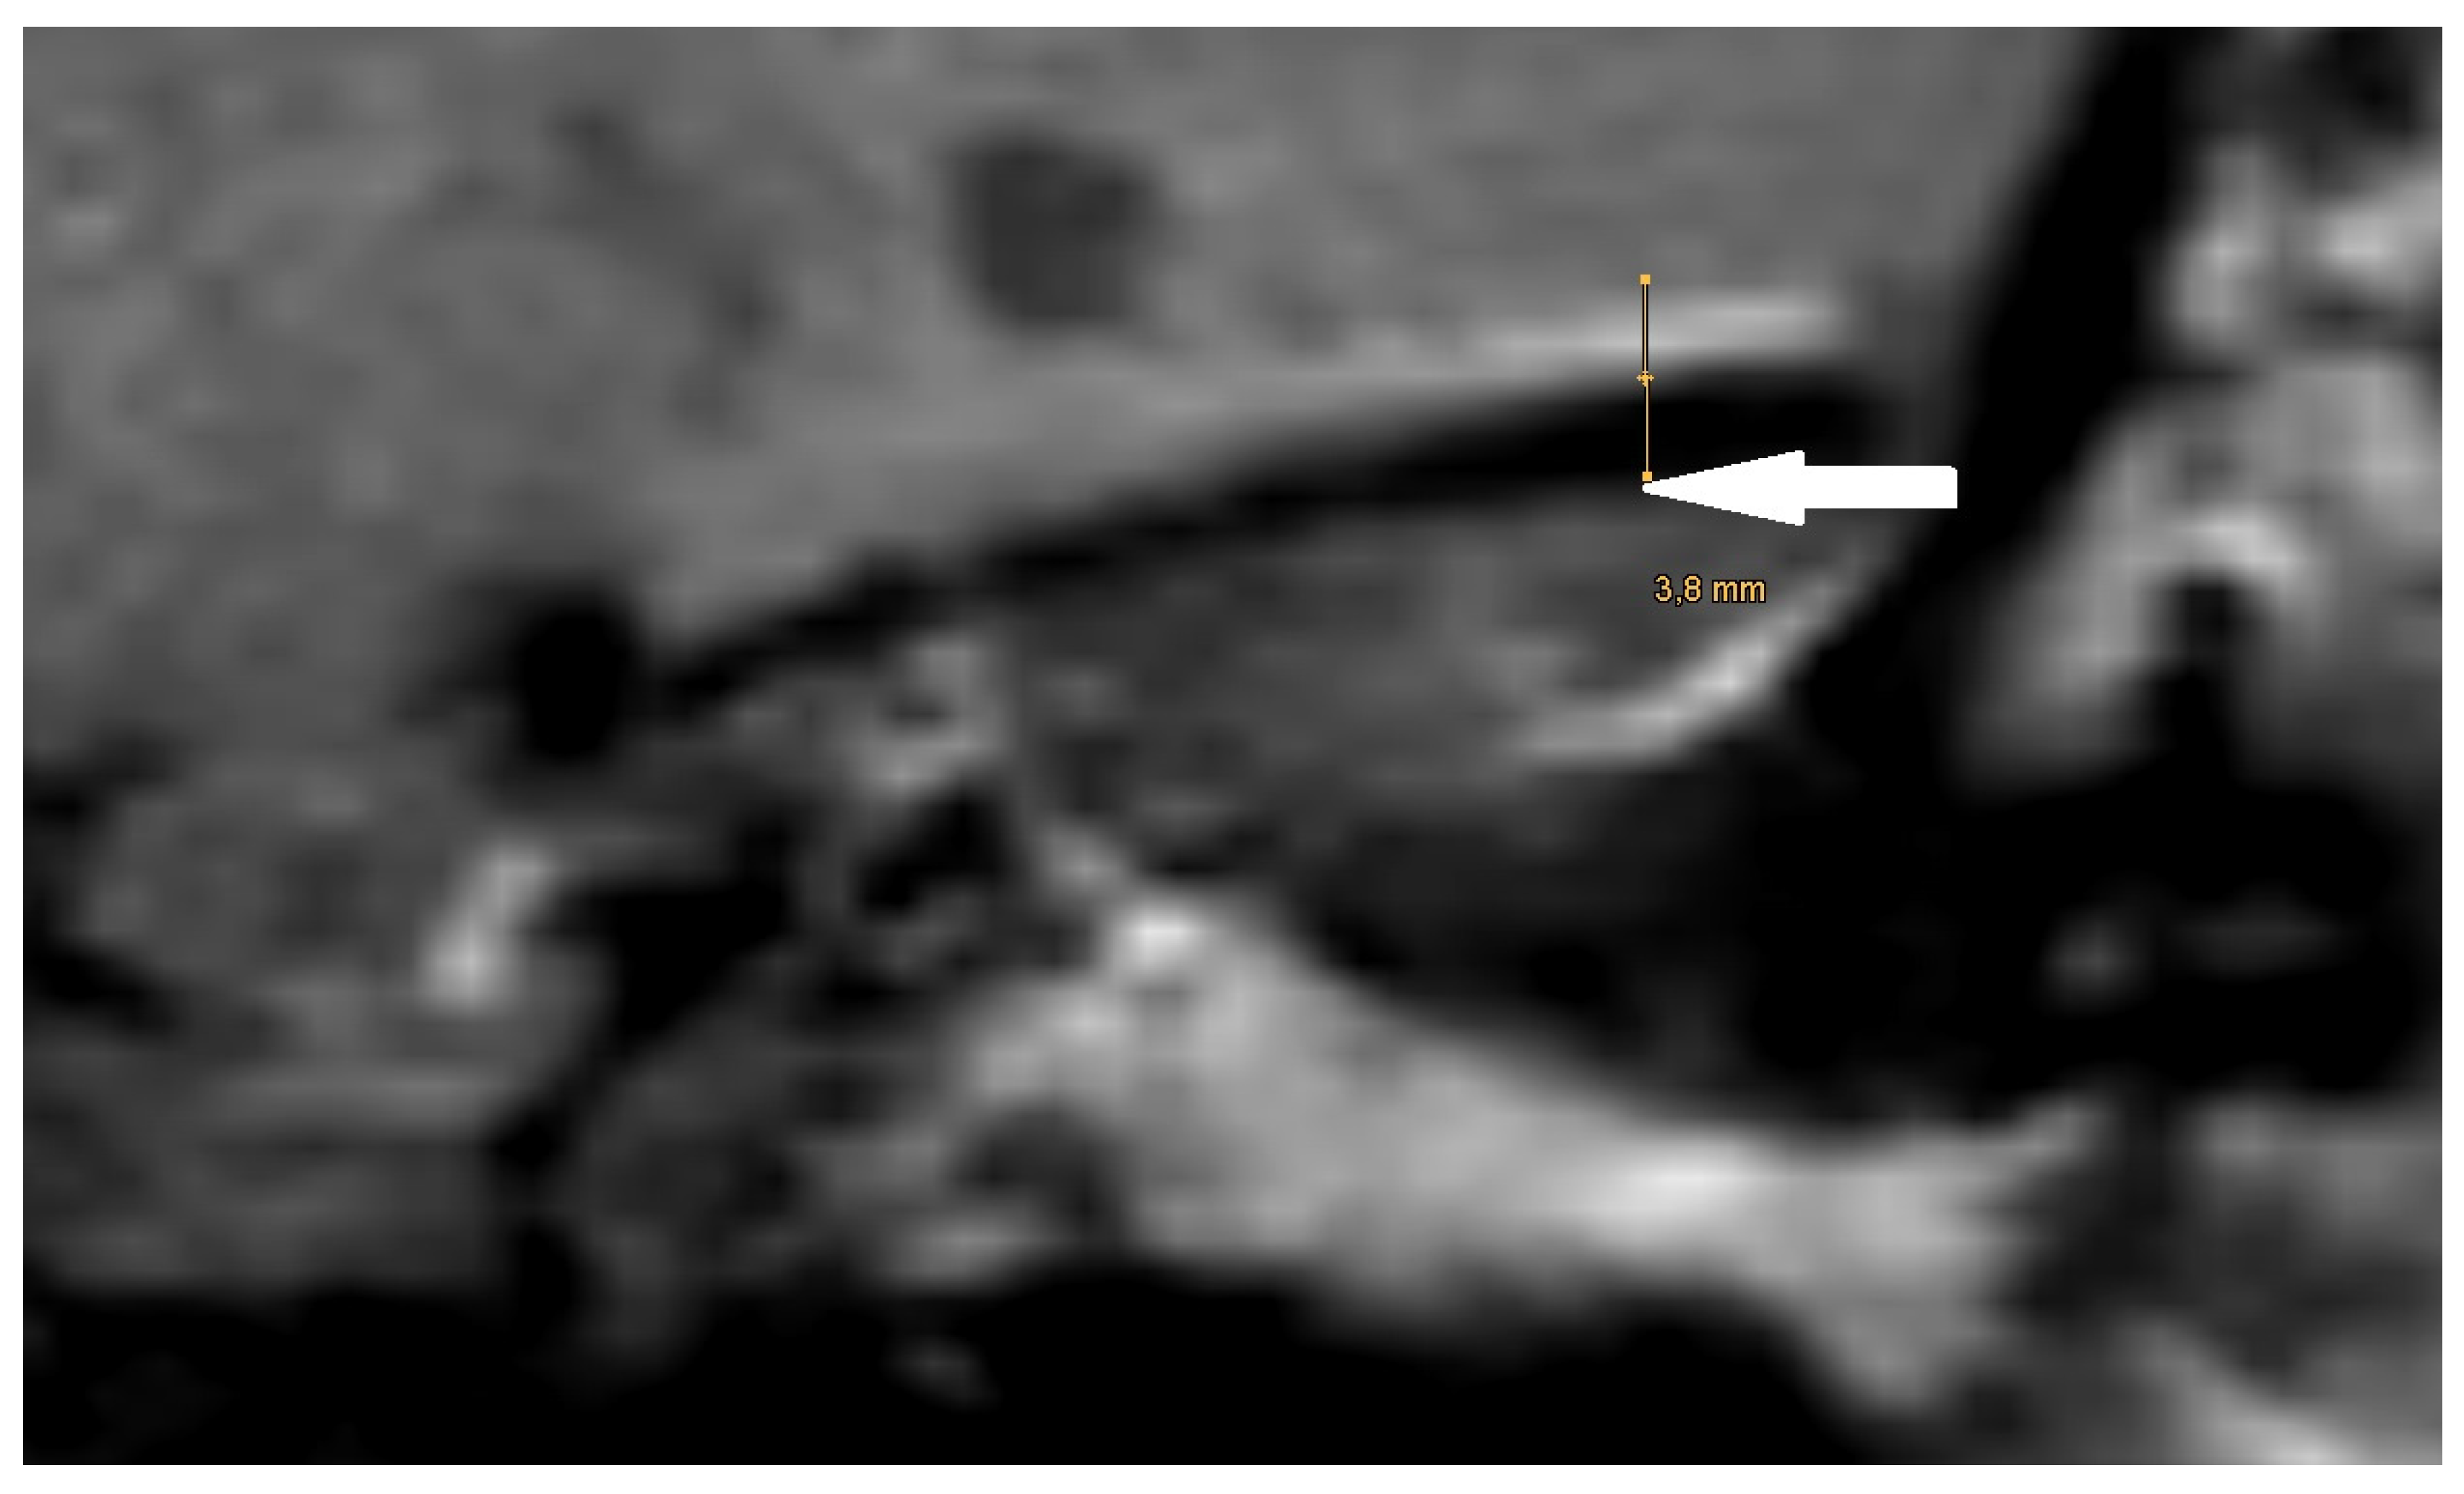

| Size of artifact | 3.60 (sd = 1.01, min = 2.50, max = 4.50) | 3.11 (sd = 0.54, min = 2.20, max = 4.50) | 4.74 (sd = 0.77, min = 3.90, max = 6.10) |

| PORP | 2.0 mm | 3.1 mm | 5.4 mm |

| TORP | 3.6 mm | 4.7 mm | 7.2 mm |

| Mesh | 0.1 mm | 3.6 mm | 5.8 mm |